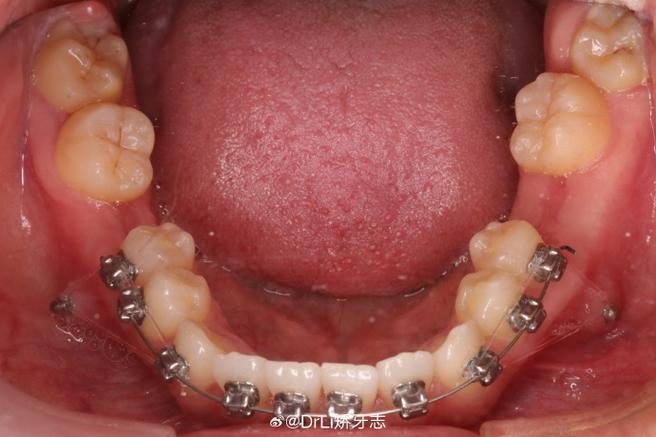

拔除“上4下5”后,正畸医生会通过固定矫治器(如金属托槽、陶瓷托槽)或隐形矫治器,施加持续、轻柔的生物力,引导牙齿按预设方向移动,具体移动机制包括:

正畸治疗:精细调整是关键

拔牙后1-2周,待拔牙创口初步愈合,即可开始戴矫治器,初期牙齿会有轻微酸胀感,属正常现象,1周内可逐渐缓解,治疗期间需特别注意口腔卫生:使用正畸牙刷、牙间刷、冲牙器清洁托槽周围,避免食物残留导致龋齿或牙龈炎;避免啃食硬物(如坚果、骨头),防止托槽脱落或弓丝变形。